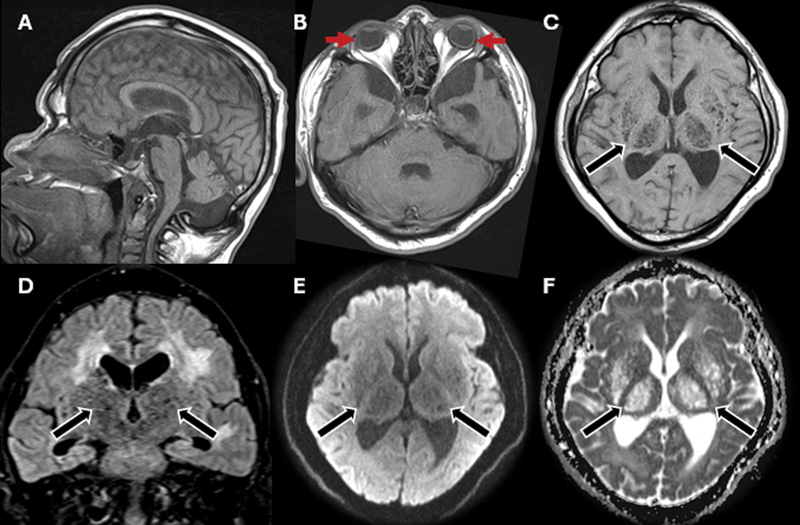

The hidden burden of lysosomal dysfunction: visual decline and microphthalmia in Hunter syndrome.